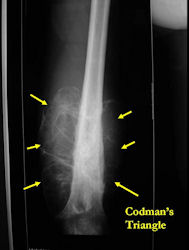

Radiographic Presentation: Conventional Osteosarcoma

There are 3 radiographic presentations for osteosarcomas, depending upon the amount of osteoid/ossification and calcium deposition:

- Mixed sclerotic and lytic, permeative lesion most common radiographic presentation

- Purely osteoblastic, permeative lesion: dense sclerosis and osteoid production

- Purely lytic, permeative lesion: little osteoid production and/or minimal calcium deposition in osteoid

Conventional osteosarcomas are permeative lesions on plain radiographs (borders of the lesion cannot be clearly delineated)

- Wide zone of transition from lytic/sclerotic areas of tumor to normal bone

- Makes borders of lesion hard to define

- Most (90%) arise from the metaphysis of the bone

- Rarely (10%) arise from the diaphysis

- Most conventional osteosarcomas (90-95%) extend through the bone into the soft tissues and form a soft tissue mass outside of the bone

- Periosteal reactions such as the Codman’s triangle are apparent at periphery of soft tissue mass